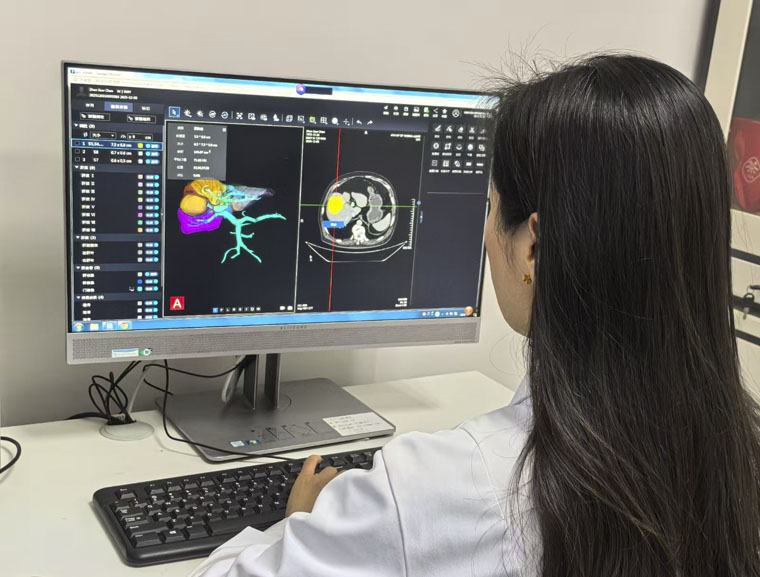

肝胆外科收治的这名患者主因皮肤黄染伴腹部疼痛数月余,综合临床症状及检查检验结果,临床医生评估患者情况十分危急,若不及时进行手术会危及生命。CT磁共振科对患者实际情况精准进行了医学影像三维重建,彩色3D图像清晰显示了肝内各个分段及肝动静脉,以及肝内肿瘤的位置、大小及与周围肝内血管、肝内胆管的关系。

术中,肝胆外科医生对照彩色3D图像,仔细剥离病灶周围肝静脉、肝动脉及肝内胆管,切除包含病灶在内的“肝右叶+右尾状叶+肝门部胆管”,保留肝左叶及周围血管组织,同时规划系统对患者残肝比等关键指标进行了定量计算,为患者术后恢复治疗提供了重要参考数据。